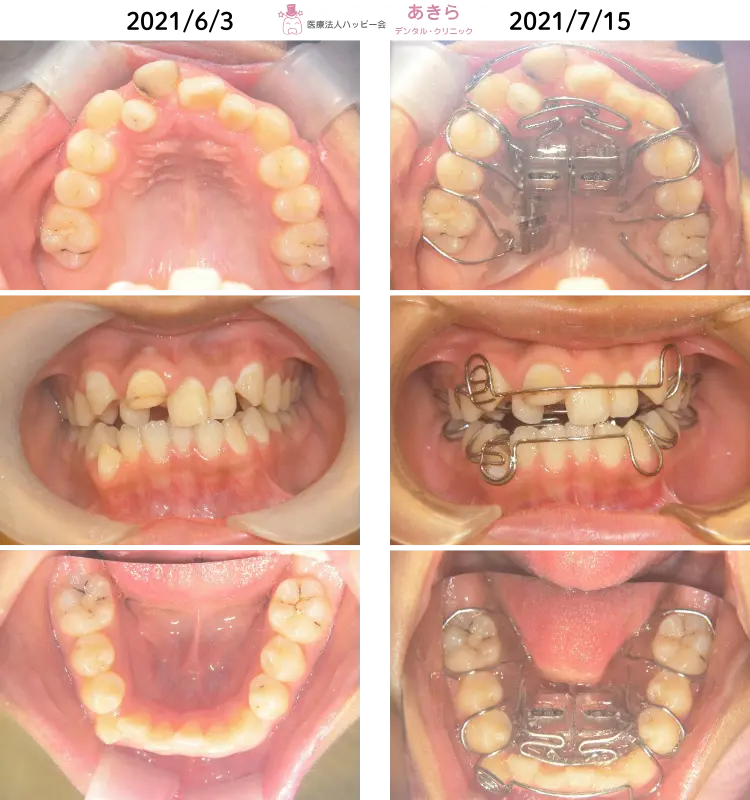

2021年6月3日 初診時 ⇒ 7月15日 SHAスタート時

上顎右側1番唇側転位

上顎右側2番舌側転位(矮小歯)

右下3番低位唇側転位

上下顎叢生

上下右側2番クロスバイト

上下顎狭窄歯列

歯牙脱灰著名